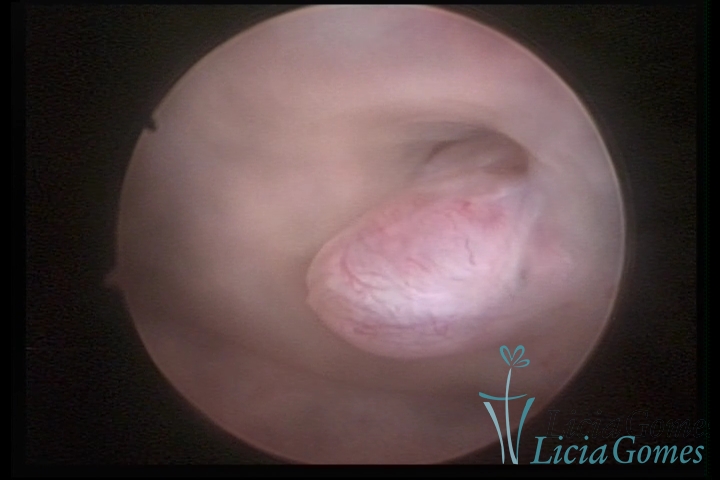

PÓLIPOS ENDOCERVICAIS

São tumores benignos, resultantes da proliferação focal reativa aos processos inflamatórios ou à situações de hiperestrogenismo, e podem ter sésseis (com a base de implantação larga) ou pediculados do epitélio.